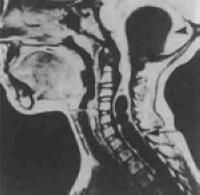

症狀體徵 疾病病因 病理生理 診斷檢查 鑑別診斷小腦扁桃體下疝畸形又名阿諾德-奇阿(Arnold–Chiari)畸形,為常見的先天性發育異常。是由於胚胎髮育異常使小腦扁桃體下部下降至枕骨大孔以下、頸椎...

疾病分類 病因病理 臨床表現 診斷 鑑別診斷小腦扁桃體下疝畸形又名阿諾德-奇阿(Arnold–Chiari)畸形,為常見的先天性發育異常。是由於胚胎髮育異常使小腦扁桃體下部下降至枕骨大孔以下、頸椎...